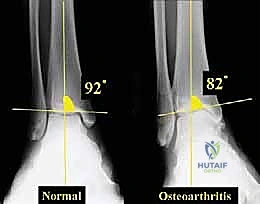

2. التصوير بالأشعة السينية بوضعية الوقوف (Weight-bearing X-rays)

هذا هو حجر الأساس في التشخيص. الأشعة العادية والمريض مستلقٍ لا تظهر الحجم الحقيقي للتشوه. يطلب الدكتور هطيف صوراً خاصة والمريض يحمل وزنه كاملاً على قدميه.

* المنظر الأمامي الخلفي (AP View): لتقييم المسافة المفصلية وتحديد زاوية سطح الساق (Tibial Anterior Surface Angle - TAS).

خشونة مفصل الكاحل من النوع التقوسي هي حالة مرضية تدريجية (Progressive) لا تحدث بين عشية وضحاها. إنها تتميز بتشوه تقوسي مع فتح أمامي للسطح المفصلي في الطرف البعيد من عظم الساق. وغالباً ما تظهر هذه الحالة بشكل ثنائي (في كلا الكاحلين)، وتكون أكثر شيوعاً لدى النساء في منتصف العمر وكبار السن، وكذلك لدى الرياضيين السابقين أو الأشخاص الذين تعرضوا لإصابات قديمة.

تكمن المشكلة الأساسية في خشونة مفصل الكاحل من النوع التقوسي في تركز الإجهاد على الجانب الإنسي. هدف جراحة قطع العظم التي يجريها الدكتور هطيف ليس فقط إيقاف هذا التدهور، بل وإعطاء الجسم فرصة لإصلاح عيوب الغضروف جزئياً عن طريق تشكيل نسيج غضروفي ليفي (Fibrocartilage) بمجرد إزالة الضغط الميكانيكي عنه.